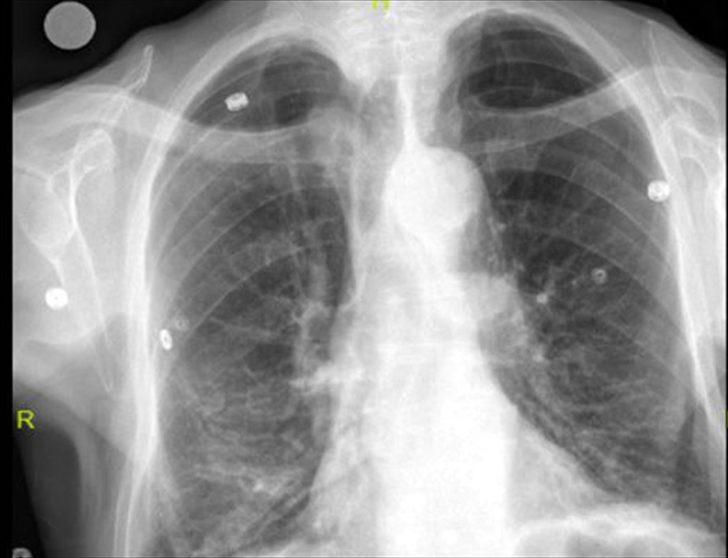

Elazığ'da öksürük ve nefes darlığı şikayetiyle hastaneye başvuran Keko Ateş'in (91) nefes borusunda 10 santimlik çivi tespit edildi. Ateş'in, 24 yıl önce Larenks kanseri ameliyatı sırasında nefes borusunda açılan açıklığı temizlemek için kullandığı çivinin soluk borusuna kaçtığı belirlendi.

Keko Ateş, öksürük ve nefes darlığı şikayetiyle Fethi Sekin Şehir Hastanesi'ne başvurdu. Yapılan tetkik ve muayenelerden sonra Ateş'in nefes borusunda çivi olduğu tespit edildi. Hastanın hayatını tehlikeye atan bu durumun giderilmesi için Ateş, Göğüs Cerrahi Uzmanı Dr. Öğr. Üyesi Murat Kılıç tarafından operasyona alındı. Soluk borusun içerisinde ve sağ akciğer içerisine doğru kaçmış olan 10 santim uzunluğundaki çivi, 'Rijit Bronskoskopi' işlemiyle çıkarıldı.

Dr. Öğr. Üyesi Murat Kılıç, Larenks kanseri olan Ateş'in, 24 yıl önce Total Larenjektomi ameliyatı sırasında boynundan nefes borusuna açılan açıklığı temizlemek için kullandığı çivinin soluk borusuna kaçtığını anlattı. Dr. Öğr. Üyesi Kılıç, "Bu nedenle gelişen öksürük ve nefes darlığı şikayeti ile önce başka bir sağlık merkezine başvuran, ardından Fethi Sekin Şehir Hastanemiz Göğüs Cerrahisi Kliniği'ne yönlendirilen hastaya çektiğimiz tomografide soluk borusu içerisinde ve sağ akciğer içerisine doğru kaçmış olan bir çivi olduğunu tespit ettik. Bunun üzerine hastamızı acil olarak ameliyata aldık. Uyguladığımız Rijit Bronskoskopi işlemi ile nefes borusundaki 10 santimlik çiviyi başarılı bir şekilde çıkardık. Hastamızı ameliyat sonrası bir süre serviste takip ettikten sonra gün içerisinde şifa ile taburcu ettik" dedi.